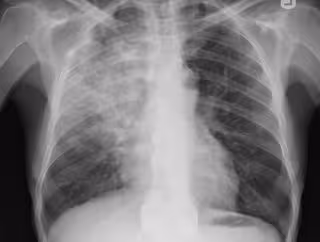

Neumonía, pulmonía, radiografía pulmones

FLICKR/YALE ROSEN - Archivo